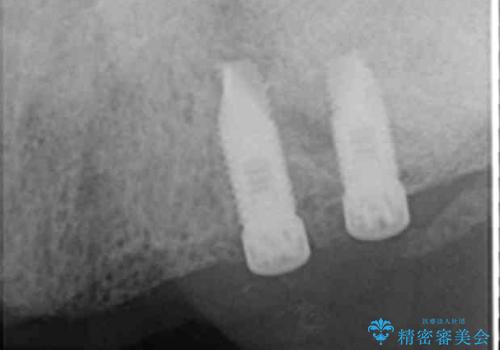

咬合関係がⅢ級(受け口)のため唇側に骨増生を行ったのちインプラント埋入(右上31左上3)を行いました。

治療途中で患者様が喫煙を再開され、最もタバコの影響を受けやすい上顎前歯部(右上31)インプラント周囲の骨吸収と少量の排膿を認めました。

長期的予後不良と判断した右上3フィクスチャーを除去し、人工骨による骨増生及び右上2に埋入を行いました。